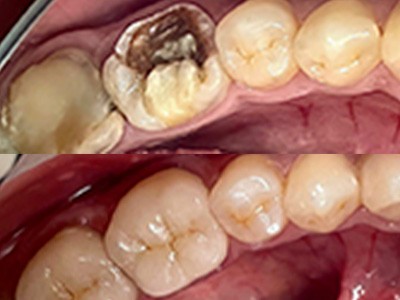

- Истории пациентов - Стоматология